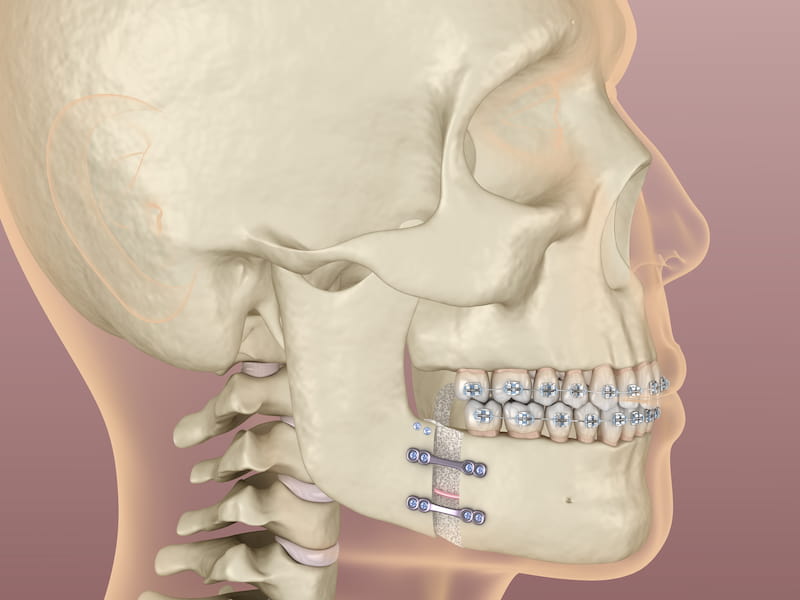

مشخصات ایمپلنت فک کامل

ایمپلنت فک کامل، راهی عالی برای جایگزین کردن دندانهای گمشده است و باعث تقویت قوس های فکی و بهبود خط بندی نیز میشود.